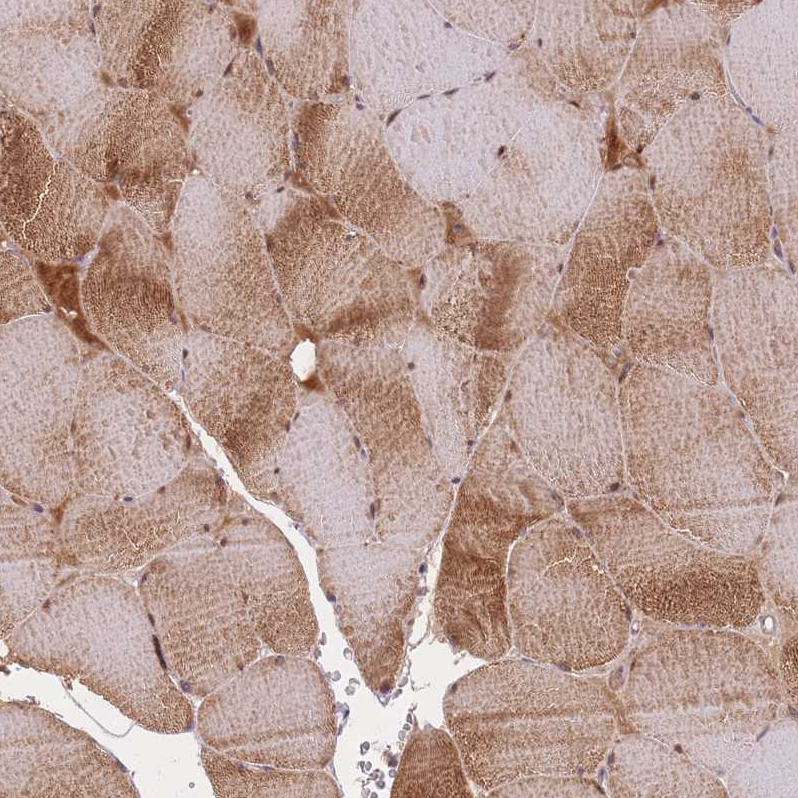

Immunohistochemical staining of human skeletal muscle shows moderate cytoplasmic positivity in myocytes.